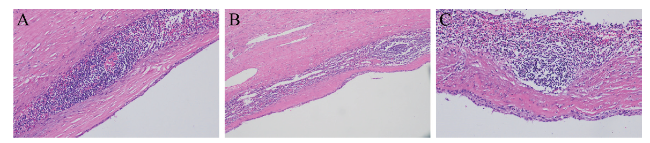

1个月后患者返院复查腹部MRI,胰腺尾部见类圆形T1WI低信号影,T2WI高信号影,DWI呈稍高信号,内壁光滑,增强扫描未见强化,考虑胰腺尾部囊性占位,良性病变以假性囊肿可能性大(图3)。患者为进一步治疗,入住我院肝胆外科,有手术指征并与患者及家属沟通后于全身麻醉下行腹腔镜胰体尾切除术+脾切除术+腹腔粘连松解,术中见胰尾处有一大小7.0 cm×8.0 cm的囊性肿物,包膜完整,质韧,活动度可,肿物与脾动静脉、主胰管间距约0.5 cm以上,其余胰腺部分质地软,胰腺周围、脾动脉淋巴结及脾门淋巴结部分未见肿大。术后病理结果:囊壁由纤维组织构成,内壁大部分区域未见被覆上皮,局部被覆鳞状上皮,囊壁内见较多淋巴细胞浸润,局部淋巴滤泡形成(图4)。最后诊断为PLEC。

图3 一例PLEC患者腹部MRI图

注:A为MRI平扫冠状位图片,胰腺尾部见类圆形T1WI低信号影,T2WI高信号影,DWI呈稍高信号,内壁光滑;B为MRI平扫横断位图片;C为MRI增强扫描横断位图片,未见强化;白色箭头所示为低密度影。

图4 一例PLEC患者病理组织切片(HE染色,×100)

注:A为囊壁由纤维组织构成;B为内壁大部分区域未见被覆上皮;C为局部被覆鳞状上皮,囊壁内见较多淋巴细胞浸润,局部淋巴滤泡形成。